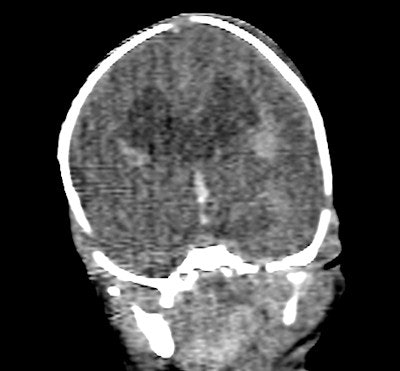

Coronal image of the brain shows dilated cerebral ventricles.Evaluation of the heart was poor on CT, as was expected in a noncontrast postmortem study, the authors reported. The heart was correctly identified as normal in fetus 5, but much of the heart could not be commented upon, and even the great vessels were difficult to confidently identify. Significant cardiac abnormalities were identified in fetuses 2 and 3 at autopsy. The diaphragm could be seen to be intact in four of the fetuses at CT, and was intact in all fetuses at autopsy.